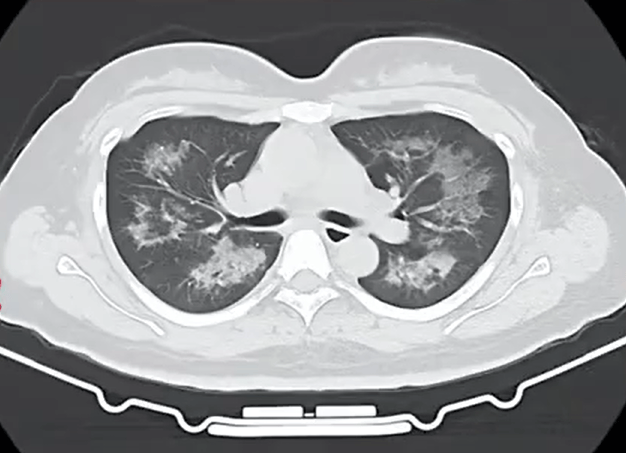

胸部CT进一步显示,她的双肺出现多发斑片状模糊影,被诊断为间质性肺炎华安创新基金。医生判断,病因很可能与她近期长期接触的某类物质相关。经过医生反复细致地询问病史,小江才说出自己存在长期、频繁使用定妆喷雾的情况。